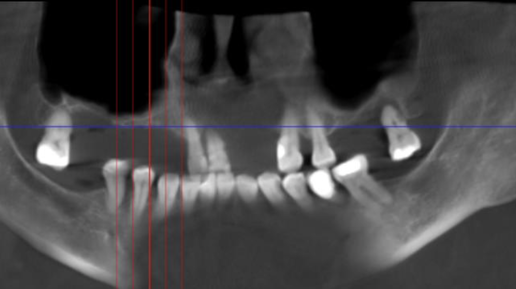

Очень часто пациенты приходят с вопросом: почему после удаления зубов им отказывают в установке имплантов? Основная причина — значительный недостаток костной ткани в верхней челюсти, который развивается со временем или связан с индивидуальными особенностями. Многие клиники просто не берутся за такие сложные случаи из-за высокого риска. Однако существует эффективное решение — процедура синус-лифтинга, о ней я расскажу подробнее далее. Синус-лифтинг — это хирургическая операция по наращиванию костной ткани в зоне гайморовой пазухи...